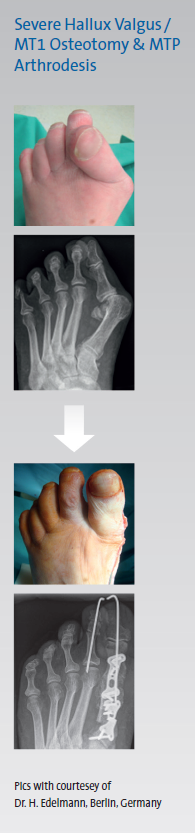

From DARCO India Innovation E-News, Issue 12, June 2016 Is there a biomechanical need for the use of a counter side height adjustment while wearing a Wedge Shoe?By wearing a wedged post-surgical or off-loading shoe, the patient will experience a bilateral asymmetry in leg length which leads to a limping gait. Patients might claim knee, hip and/or lower back pain after wearing a wedged shoe for a while due to a changed biomechanical function chain.It looks like the human body can tolerate a leg length difference up to 2 cm (1). Differences of more than 2 cm can lead to difficulties in walking. Even patients without diabetic ulcers and/or neuropathy often claim pain in the Sacroiliac Joint. In Berlin Germany, Dr. Edelmann observed 100 patients in a period of 8 months who underwent a Hallux Valgus correction surgery and had to wear a forefoot off-loading shoe.